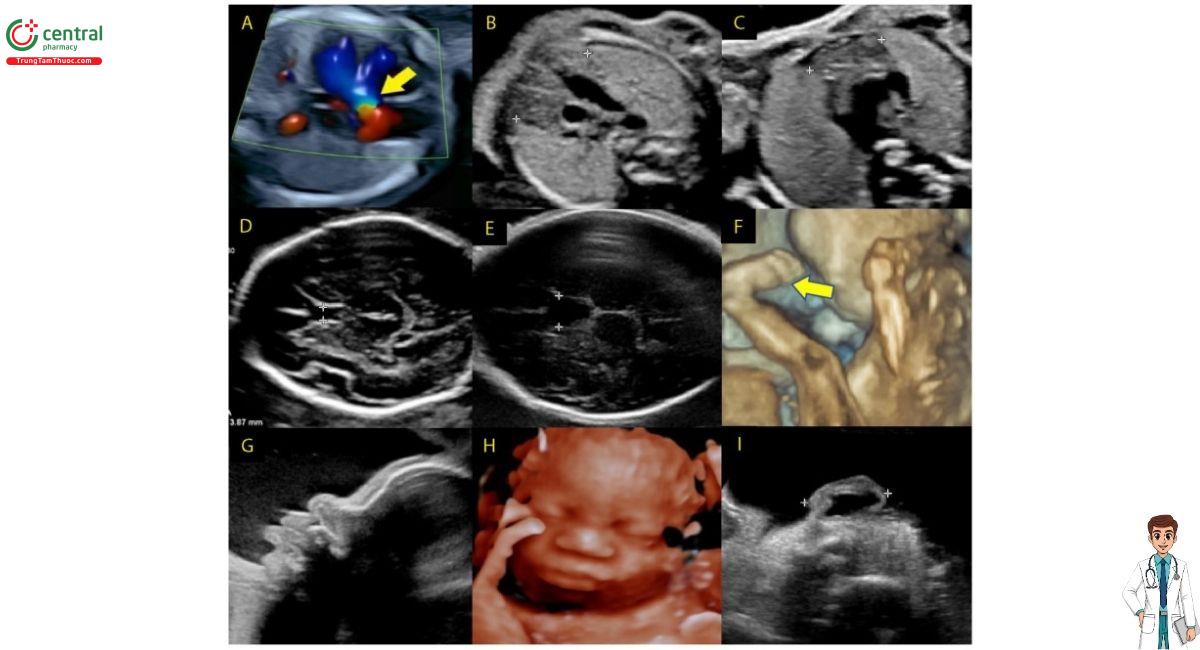

( A ) Tứ chứng Fallot, động mạch chủ đè lên (mũi tên),

( B ) tuyến ức bình thường, ( C ) tuyến ức thiểu sản,

( D ) vách ngăn trong suốt (CSP) bình thường,

( E ) CSP mở rộng, ( F ) bàn chân khoèo (mũi tên),

( G ) nhìn nghiêng với mũi củ hành, ( H ) khuôn mặt với mũi củ hành,

( I ) tai nhỏ với xoắn ốc dày gấp lại. ( B đến E —các vùng quan tâm được chỉ ra bằng compa).